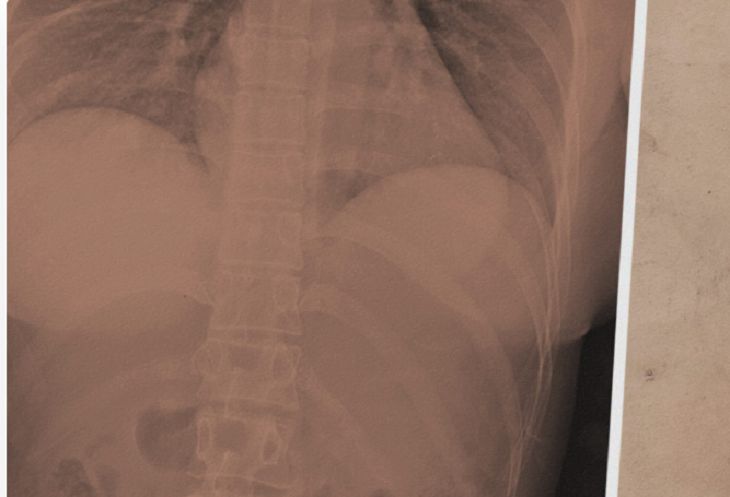

Оказалось, что снаряд прошел через левый имплантат и поменял свою траекторию так, что не задел сердце.

Пуля столкнулась с силиконом, который перенаправил ее к правому кусочку силикона, да с такой силой, что перевернул его вверх ногами.

После чего, она вошла в грудную ткань, где и застряла.

Правда, без последствий не обошлось: у женщины диагностировали перелом ребра с правой стороны грудной клетки.